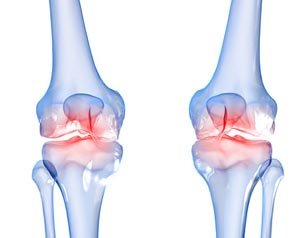

퇴행성 관절염은 나이가 들면서 자연스럽게 발생하는 관절의 마모로 인해 많은 사람들이 고통을 겪고 있는 질환입니다. 통증과 불편함 때문에 일상 생활에 큰 지장을 주기도 합니다.

약물 치료와 수술

심한 경우에는 약물 치료나 수술이 필요할 수 있습니다. 비스테로이드 항염증제(NSAIDs)는 통증과 염증을 줄이는 데 효과적이며, 경우에 따라 스테로이드 주사를 고려할 수 있습니다. 마지막으로, 관절이 심하게 손상된 경우 관절 치환술 같은 수술적 방법이 필요할 수 있습니다. 이러한 방법은 의사와 상담하여 결정하는 것이 중요합니다.